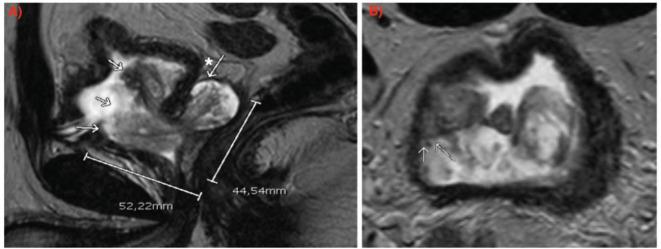

Prostate stromal tumour of uncertain malignant potential is a term used to describe a specialised proliferation of stromal cells within the prostate, most tend to be benign, but some can present with local invasion or progress to prostatic stromal sarcoma with distant metastasis. Fortunately, they represent less than 1% of prostate cancers and only a few cases have been described in the literature. We report a case of a 39-year-old male patient who was referred to our centre with this recent diagnosis in the context of acute urinary retention. After an interdisciplinary consideration, a radical prostatectomy was decided for treatment.

前列腺恶性潜能不确定的间质瘤是一个用于描述前列腺内间质细胞特殊增殖的术语,大多数倾向于良性,但有些可出现局部浸润或进展为伴有远处转移的前列腺间质肉瘤。幸运的是,它们占前列腺癌的比例不到1%,文献中仅描述了少数病例。我们报告一例39岁男性患者,因近期在急性尿潴留情况下诊断为此病而转诊至我们中心。经过多学科会诊后,决定行根治性前列腺切除术进行治疗。